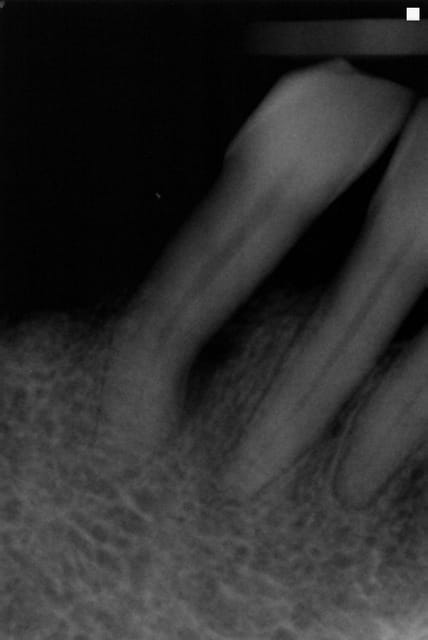

une patiente qui présente une lésion sur le coté mésial de la racine de 43, il ne s'agit pas d'une lésion paro, en tout cas au sondage impossible de rejoindre la lésion.

La dent est vivante, légèrement sensible à la palpation vestibulaire, sensible a la pression axiale, et surtout siège de douleurs fréquentes, notamment à la mastication, surtout du fait qu'elle soit support de crochet de PAPCM.